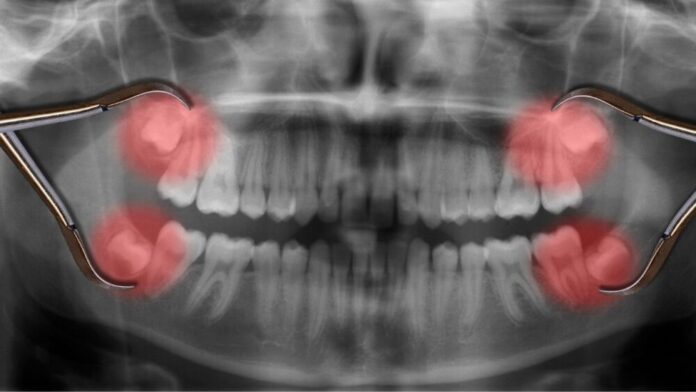

Dois casos recentes destacam que procedimentos odontológicos aparentemente simples podem levar à morte. Em Goiânia, Luan Vinícius Alves Gonzaga, de 32 anos, faleceu após complicações de uma extração de três dentes do siso, desenvolvendo infecção generalizada e choque séptico. Já em Porto Feliz (SP), Isadora Belón Albanese, de 18 anos, morreu vítima de sepse após remover os sisos em duas cirurgias, mesmo sendo uma paciente saudável.